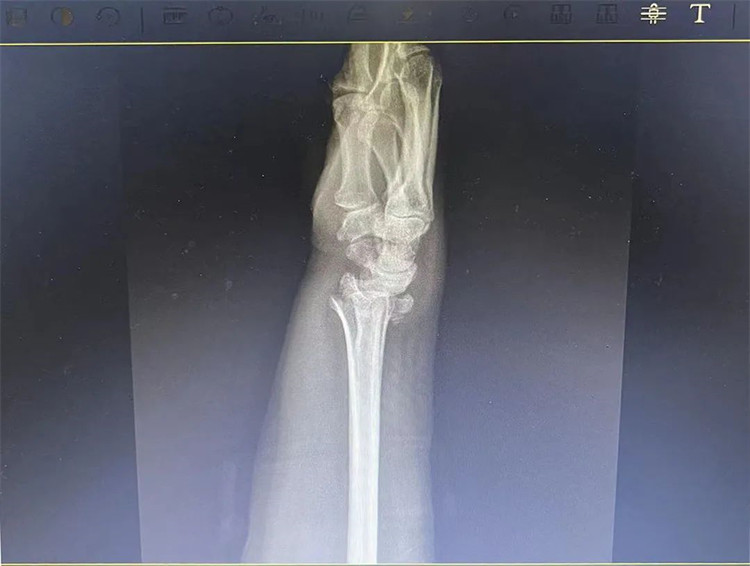

患者老年女性,50多歲,在騎電動車停下時因電動車倒下,右手著地,當即感覺,右腕及骶尾部腫痛伴右關節(jié)畸形、活動受限,急來我院就診。門診醫(yī)師結合病史、查體及輔助檢查后,診斷為:右橈尺骨遠端骨折、骶尾部挫傷并收入住院部。